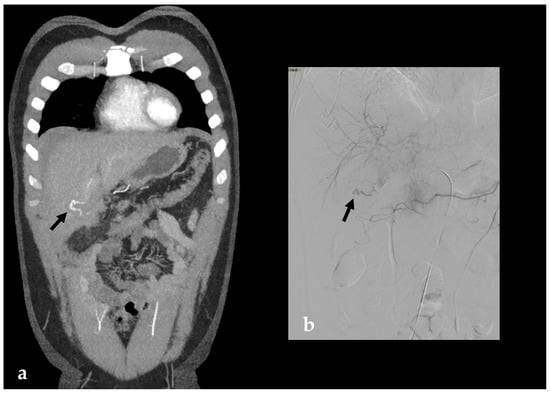

2. Imaging

3.1.3. Imaging and Diagnostic Findings

3.1.4. Management and Outcomes